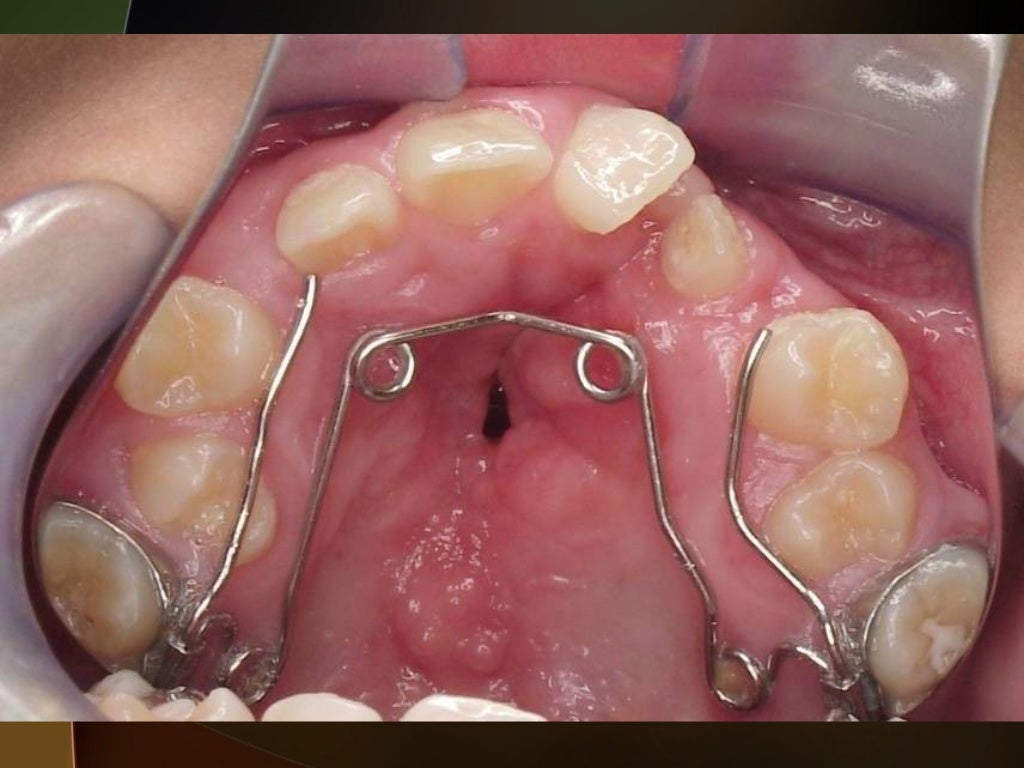

Ideal treatment protocol for cleft lip and palate patient from mixed to Presurgical Orthodontics For Cleft Lip And Palate cleft lip and palate represent one of the great challenges of craniofacial surgery, with initial descriptions of the condition and surgical. active presurgical infant orthopedics for unilateral cleft lip and palate: evidence shows that among the various craniofacial anomalies, cleft lip and palate (clp) occurs most commonly affecting 1. Presurgical Orthodontics For Cleft Lip And Palate.